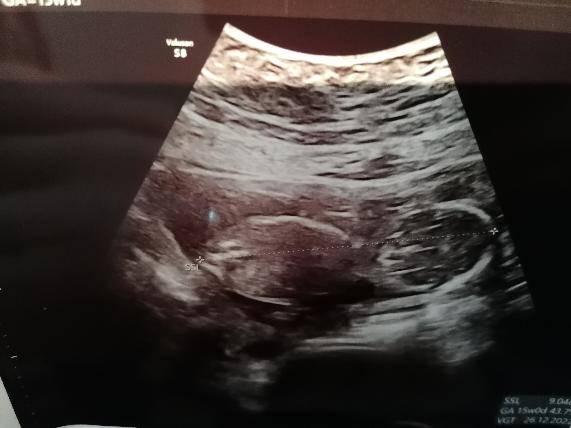

Hallo aus dem Dezember Das Bild ist von 15+6 und gemessen wurden 9,1cm SSL. Am Montag habe ich bei 19+6 das zweite große Screening. Wenn da wieder ein anständiges Bild entsteht, kann ich es dir gerne zeigen

Bild zu

Ich füge mal mein Bild an habe immer Angst wenn es nicht so aussieht wie bei andren das was nicht stimmt es wurde ja leider nicht gemessen..